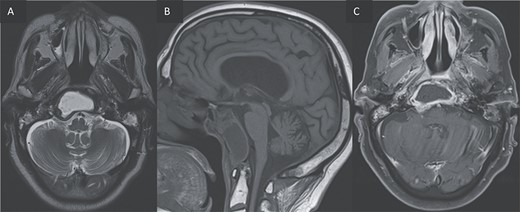

For better diagnostic assessment, the patient underwent a magnetic resonance imaging (MRI) (Figs 3 and 4), it showed the following findings:

Furthermore, inflammatory changes were noted to extend into the petrous, tympanic, and mastoid segments of the right temporal bone, as well as involving the petrous and mastoid regions of the left temporal bone and the occipital bone. Additionally, small abscess cavities were observed within the right occipital condyle.

T2 coronal (A) and T1 post gadolinium axial images (B, C) showing the extension of the inflammation around the clivus and in the petrous, tympanic, and mastoid portions of the right temporal bone with small abscesses along the mastoid cells and the occipital bone.